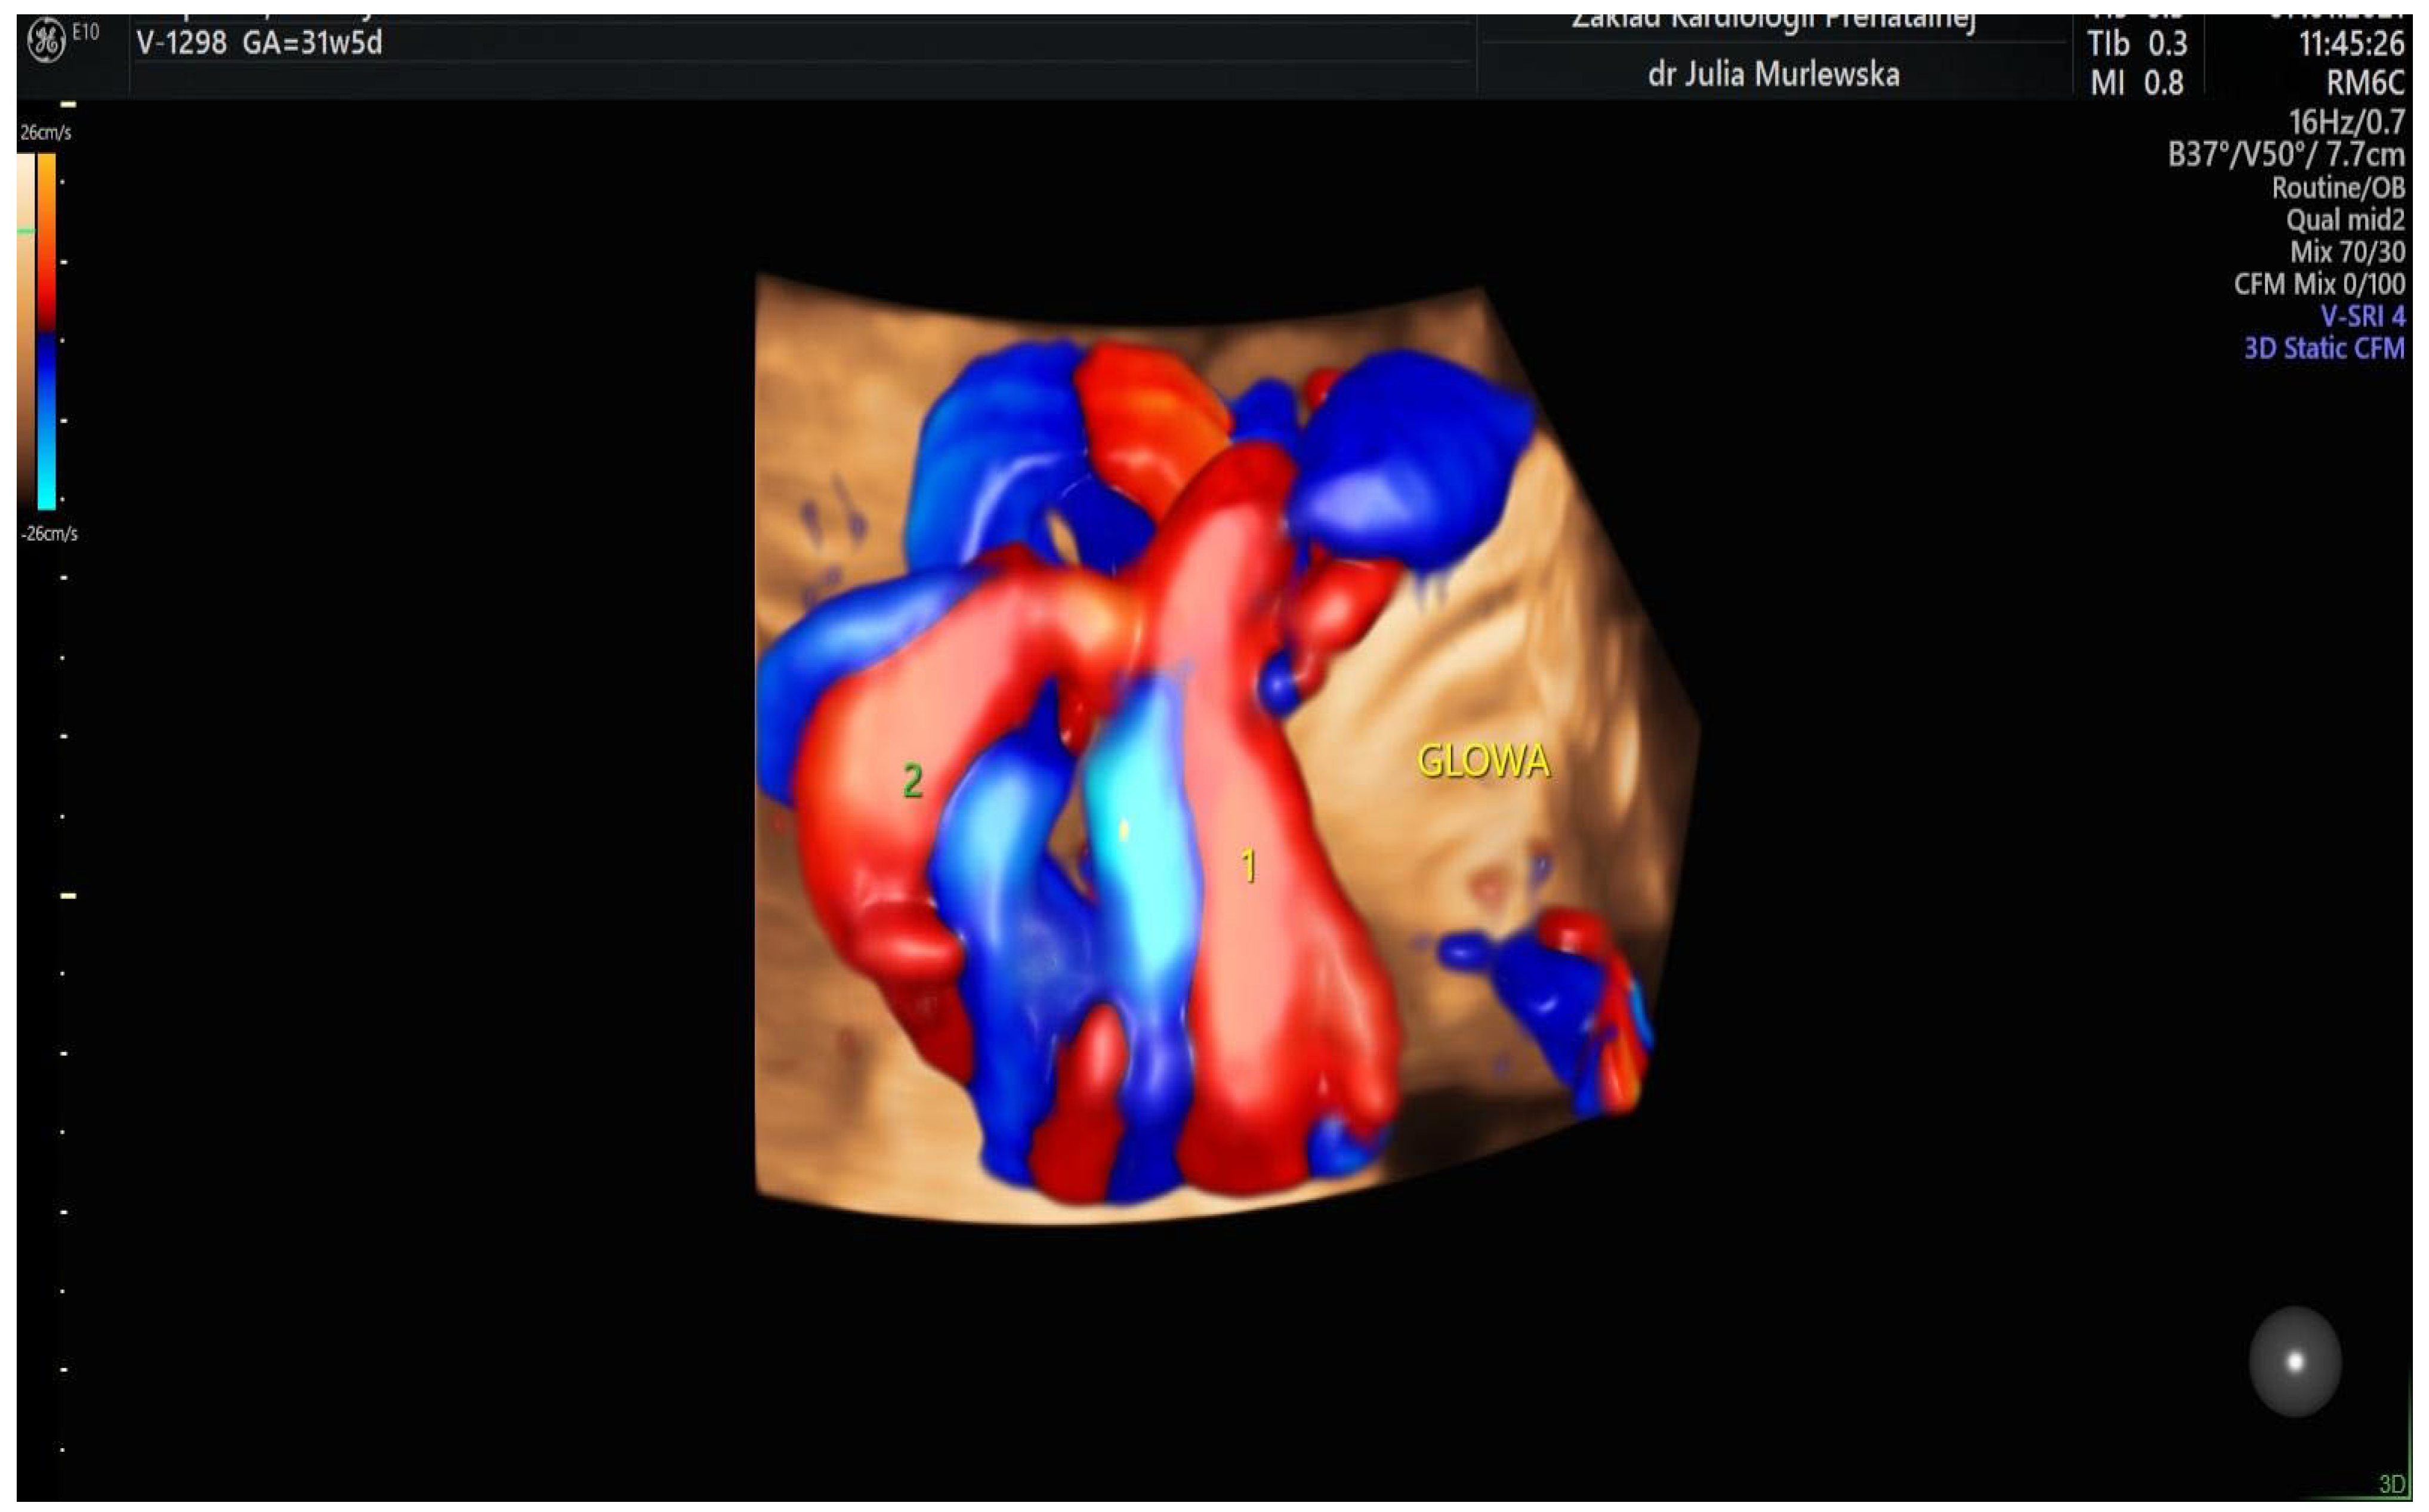

| Color Doppler |